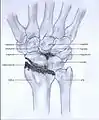

Stages

Post-traumatic osteoarthritis can be classified into four stages.[1][6] These stages are similar between SLAC and SNAC wrists. Each stage has a different treatment.

- Stage I: the osteoarthritis is only localized in the distal scaphoid and radial styloid.

- Stage II: the osteoarthritis is localized in the entire radioscaphoid joint.

- Stage III: the osteoarthritis is localized in the entire radioscaphoid joint with involvement of the capitolunate joint.

- Stage IV: the osteoarthritis is located in the entire radiocarpal joint and in the intercarpal joints. It also may involve the distal radio-ulnar joint (DRUJ).

Stage III

Stage IV